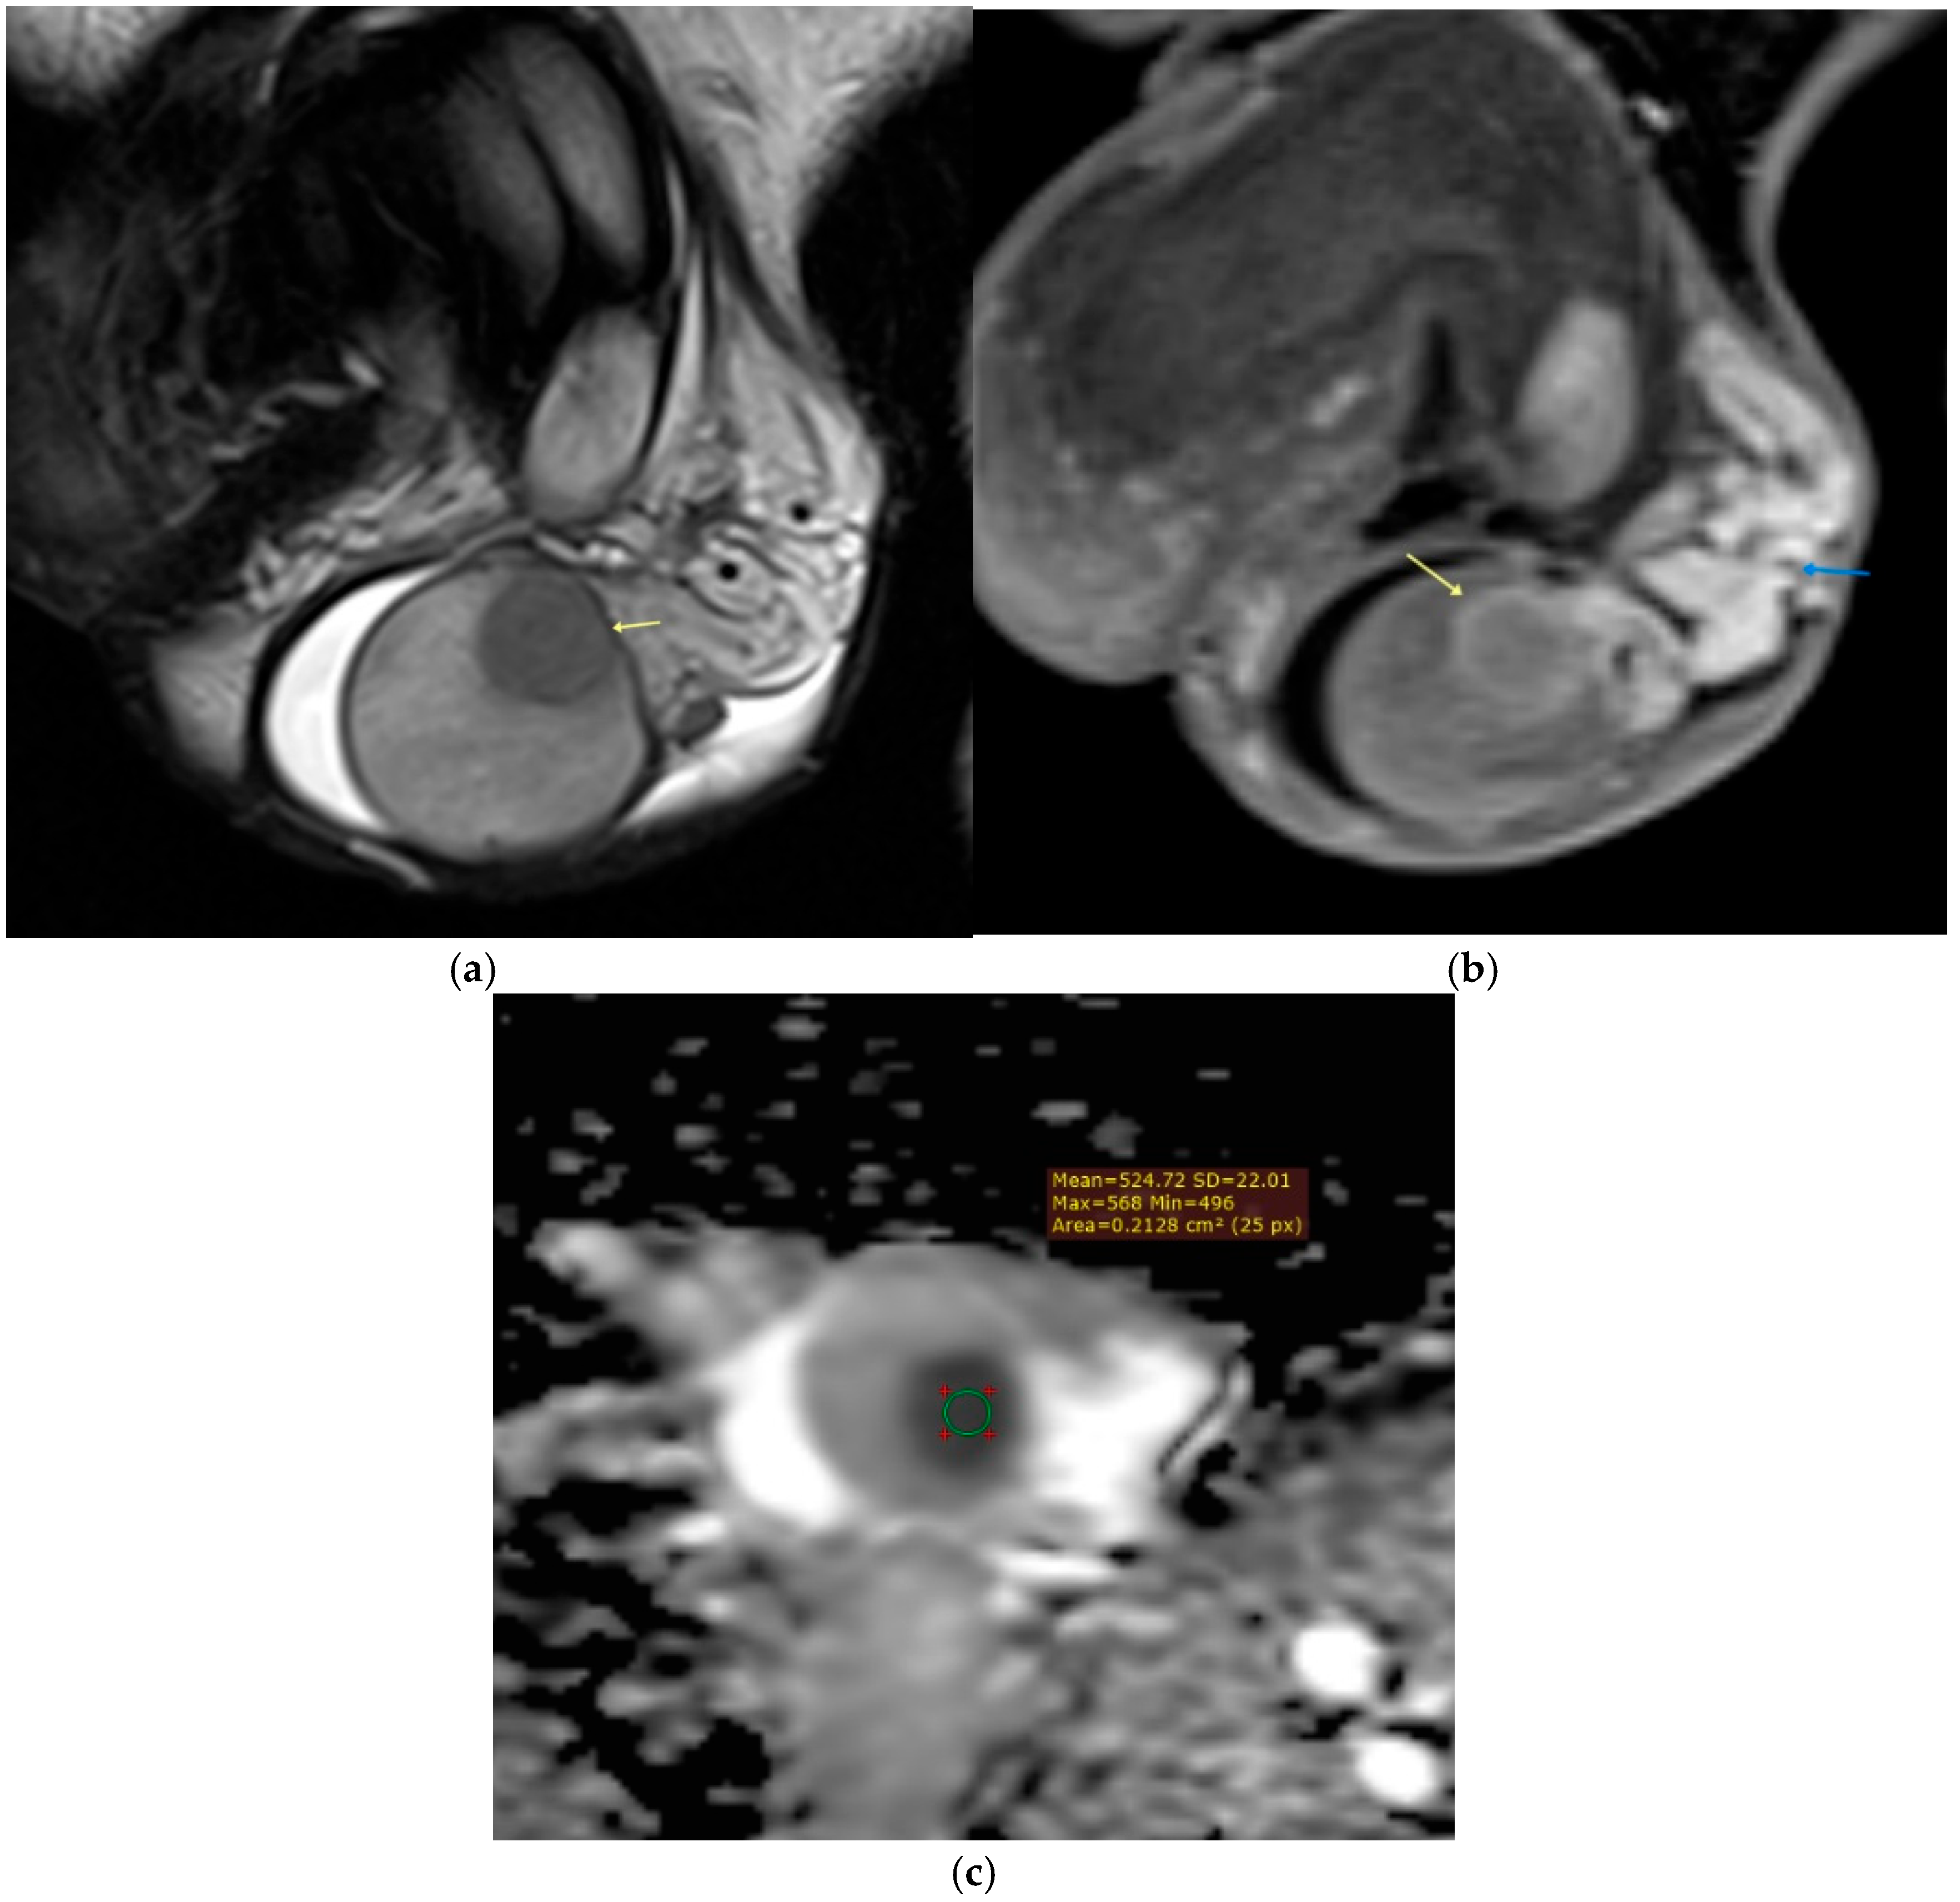

3.3.1. Intratesticular Masses

- Tsili, A.C.; Sylakos, A.; Ntorkou, A.; Stavrou, S.; Astrakas, L.G.; Sofikitis, N.; Argyropoulou, M.I. Apparent diffusion coefficient values and dynamic contrast enhancement patterns in differentiating seminomas from nonseminomatous testicular neoplasms. Eur. J. Radiol. 2015, 84, 1219–1226. [Google Scholar] [CrossRef]

- Maxwell, F.; Savignac, A.; Bekdache, O.; Calvez, S.; Lebacle, C.; Arama, E.; Garrouche, N.; Rocher, L. Leydig cell tumors of the testis: An update of the imaging characteristics of a not so rare lesion. Cancers 2022, 14, 3652. [Google Scholar] [CrossRef]